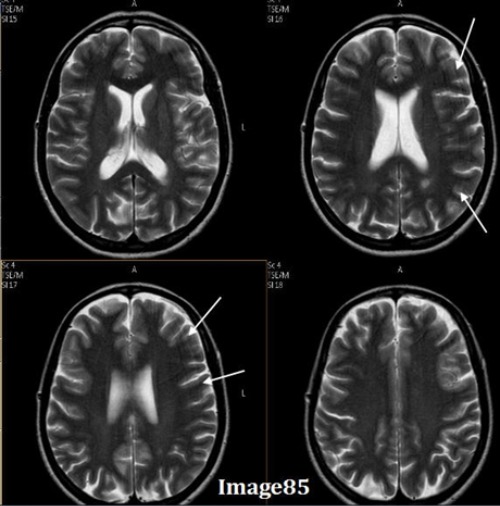

To correct for the Gibbs truncation artifact (white arrows) seen in the spinal cord in Image 85, the technologist should:

A. Decrease phase matrix

B. Increase phase matrix

C. Increase voxel size

D. Enable flow compensation

E. Utilize gating techniques

The arrows in Image 85 point to ringing lines parallel to the sharp boundary of the spinal cord. What kind of artifact is this?

A. Motion/ghosting in the phase direction

B. Gibbs truncation

C. Dielectric effects

D. RF zipper